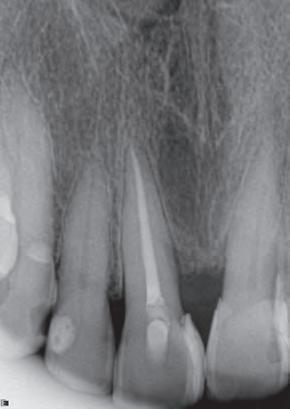

P.O. Inmediato

Prof. Dr. Warley Tavares

12/2017

Masculino

45 años

P. O. 3 meses

Reabsorción, Necrosis, Periodontitis Apical Crónica.

Instrumentación con NiTi, Hipoclorito de Sodio 2,5%, medicación con Hidróxido de Calcio por 10 días. Obturación con gutta percha y BIO-C® SEALER.

03/2018